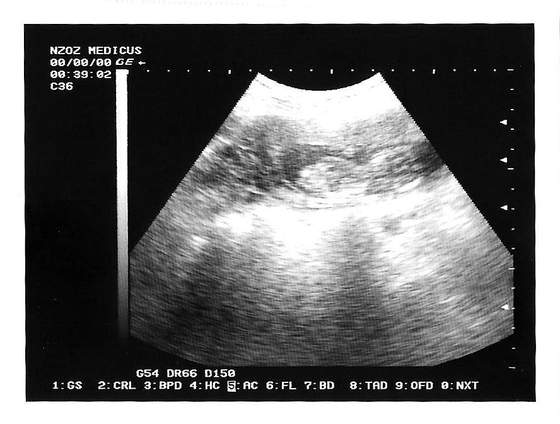

Nasze fasolki na USG

a o to moje dzieciątko, cały czas się wiercił i ciężko było pstryknąć :)

18-11 , 12 t i 3 d

Jesli tak to poniżej (powyżej??) znajduje się fotka mojego robalka w sprzed jakichś dwóch godzin. Fikał jak szaleniec, ale niestety jakośc fotki nie umywa się do Waszych :-( Cóz....wieś ma swoje plusy i minusy ;-)

• usg 13t.jpg

usg 13t.jpg

28,8 KB · Wyświetleń: 84